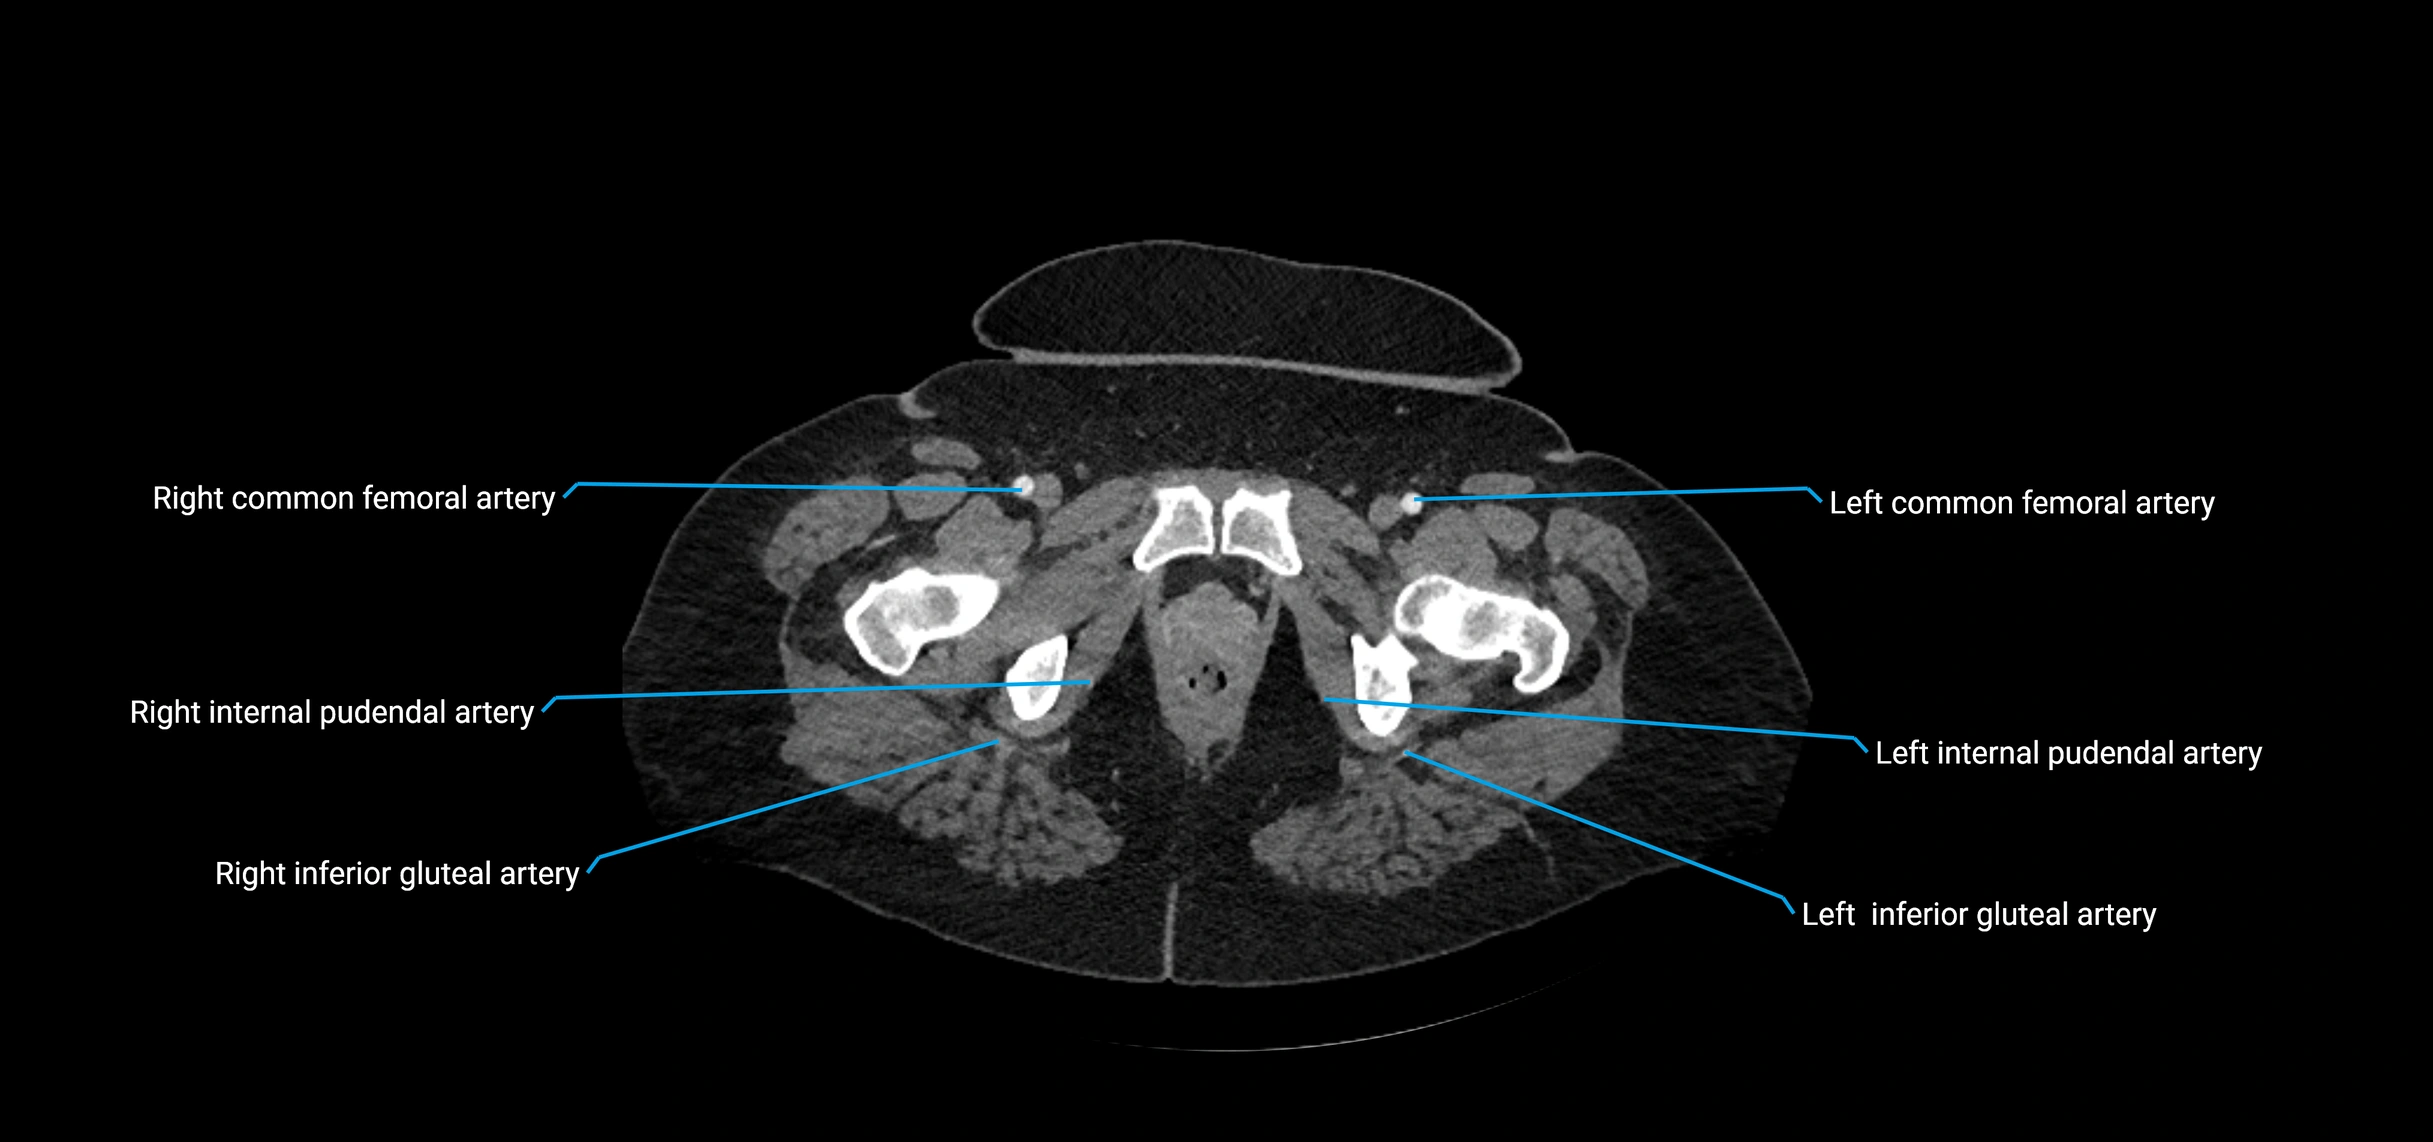

Contrast-enhanced CT (CTA):

• Gold standard for abdominal aortic imaging

• Provides excellent detail of lumen, wall, aneurysm, thrombus, and branch vessels

• Multiplanar and 3D reconstructions help in aneurysm measurement, stent graft planning, and dissection evaluation